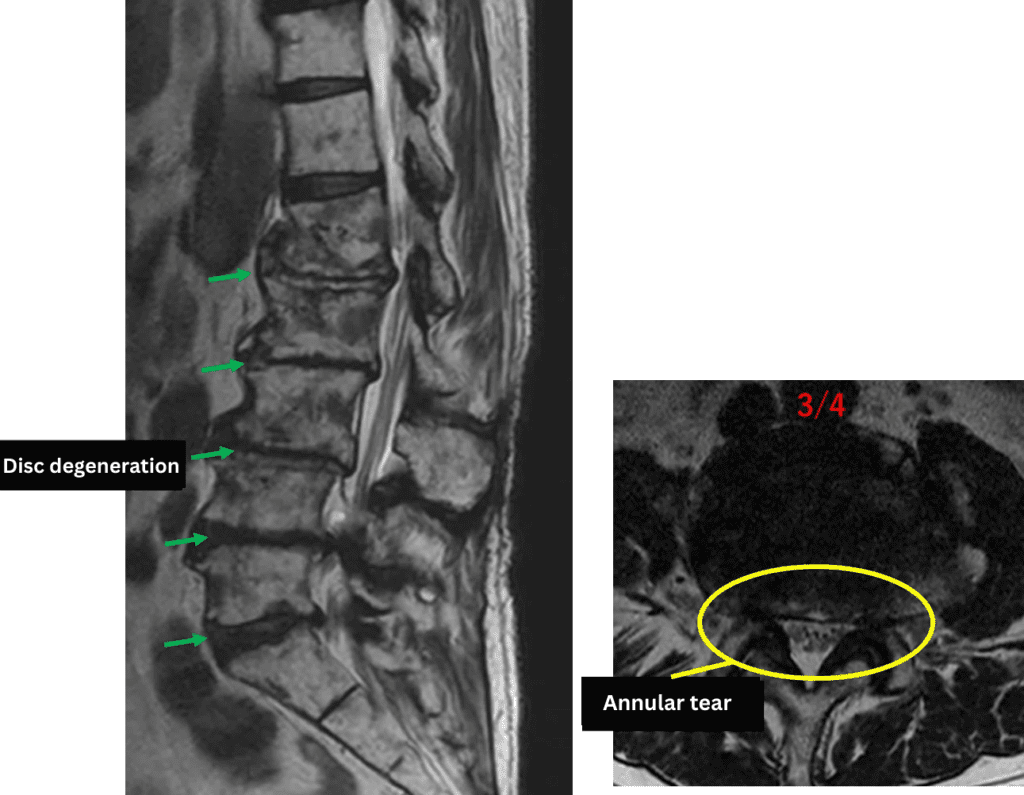

L1/2: Disc degeneration, loss of disc height

L2/3: Disc degeneration, loss of disc height

L3/4: Disc degeneration, loss of disc height, annular tear

L4/5: Disc degeneration, bulging, right foraminal stenosis

L5/S: Disc degeneration, bulging

The above findings were also observed on the imaging.

Based on these findings, disc degeneration, loss of disc height, bulging, annular tear, and foraminal stenosis at L3/4, L4/5, and L5/S were considered the most likely causes of the patient’s primary symptoms.